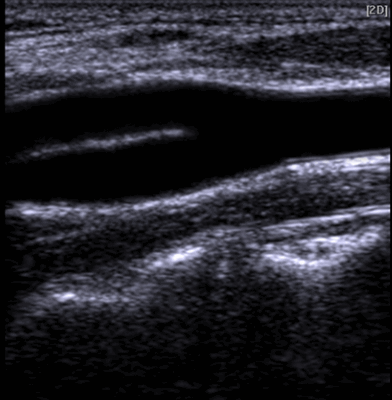

Что лучше МРТ или УЗИ сосудов шеи?

Ультразвуковая диагностика базируется на способности волн проходить через ткани различной плотности и отражаться с определенной скоростью. Это и есть «эхо», которое регистрирует датчик. Затем компьютерная программа преобразует сигнал в изображение.

УЗИ сонной артерии в месте бифуркации

Что лучше, МРТ или УЗИ, для диагностики патологий шейных сосудов, определяет врач. Оба метода считаются абсолютно безопасными и нужными. УЗИ занимает меньше времени и не требует ограничений подвижности, тогда как МРТ дает более полные сведения о состоянии всех структур шейного отдела. Ультразвуковые методики подходят для экспресс-диагностики, а томография оптимальна для выяснения природы заболевания и сбора дополнительных сведений.

Врачи предпочитают УЗИ, если для определения патологии решающее значение имеет скорость кровотока в сосудах шеи. МРТ предоставляет важную информацию, если есть подозрения на поражения стенок артерий/вен или мягких тканей, которые могут привести к острым нарушениям мозгового кровообращения.